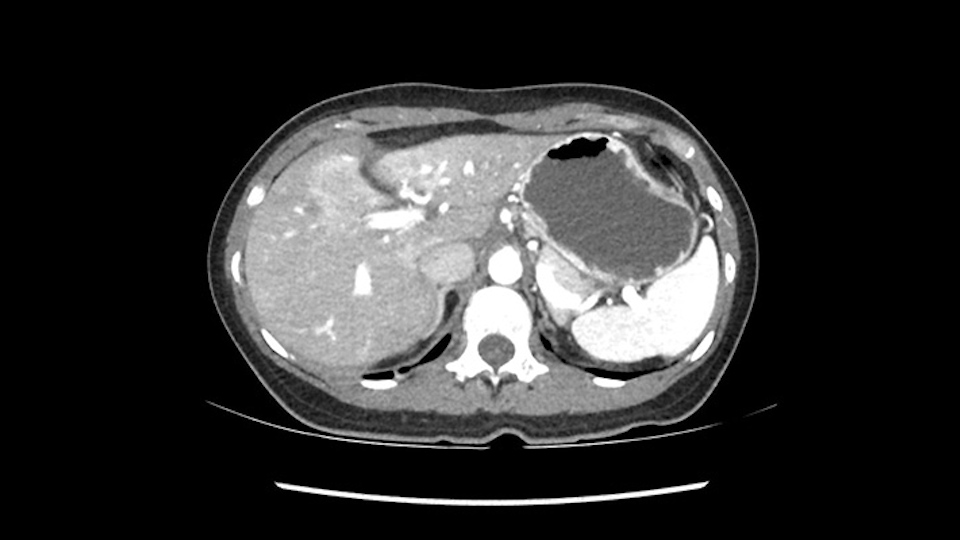

So if we look at the CT scan, on the axial, it’s a larger lesion. It’s about 6 or 7 or 8 centimeters. So it does look a bit threatening in terms of its resectability but if you really drill down deeply into the anatomy, and I think the coronal [imaging] is even better, you can see that the entire mass is on the patient’s left side of the falciform ligament. So it’s really only a left-sided tumor and not even really a left-sided tumor because Segment 4 is uninvolved anatomically.

None of the parenchyma is affected and this tumor is very exophytic; like many Hepatitis B hepatomas; and otherwise is resectable with either a wedge resection part of Segment 2-3 or a formal left lateral segmentectomy.

Some of my colleagues thought it may be involving Segment 4 and we’d need a formal left hepatic lobectomy, dividing anatomically: the left portal vein, left hepatic artery, left bile duct. But I didn’t think so, but you can see there is a challenge in terms of being certain where this tumor is located. So we’re prepared to do any of those 3 but my person view is that its going to be an exophytic tumor off of the left lateral segment and probably a wedge.

As I review the CT scan, we have both arterial and venous phases, the tumor is obvious. But I’ll start by saying that the liver itself does not appear to be cirrhotic to my eye. It’s got a normal contour and allied to that, that I do not see evidence of portal hypertension. The spleen is normal, there’s no collateral vessels. The tumor itself, I measured maximally at about 11 centimetres in diameter and I’m told the alpha fetoprotein is very high (over 10000), which is entirely consistent with this being a solitary hepatocellular carcinoma that is very exophytic. It seems to emanate off the inferior margin of Segment 3 (because that’s the falciform). I’ll start by saying that this is not transplantable. The tumor exceeds our guidelines for transplantation, but it's likely resectable based on normal liver and no portal hypertension.

So the issue with regards to resection. A left sided tumor. I believe I can see the falciform ligament right here so we’re looking at a resection of Segments 2, 3 of the left lobe of the liver. The left portal vein is right there. I think we’ll be wiser to take the left portal vein and therefore get well into Segment 4 and do a left hemihepatectomy. Certainly, one does not need to take the middle hepatic vein; it’s miles from the tumor.

We note that the tumor is pushing on the gallbladder but I think that’s probably external for the most part. I think that’s extrahepatic. I believe that Segment 4b is probably free of tumor. I’d have to say that it's tempting, particularly looking at the coronals, to consider a very limited resection. Where you’d just chip it off the bottom of Segment 3 and do a limited Segment 3 resection. I’d be concerned about the oncologic margins. I believe that the best oncologic operation will be to take the left portal vein to get this. Certainly, she’s got plenty of liver and she’d be able to sacrifice Segments 2-3 of the left lobe of the liver. It’s not necessary to take too much of thus of Segment 4a. But once one takes the portal vein, that will be compromised. So I would do a left hemihepatectomy on this woman.

Hi my name is Sedat Karademir. I’m from Ankara Guven Hospital and I’m an HPB and transplant surgeon. We are discussing about the case I reviewed the CT of 41 year old lady with a suspected hepatoma in the left lateral segment. Presumably its Segment 3. It looks like a big tumor sitting exophytically mostly out of the liver and pressing on the surrounding organs, but it doesn’t look like any invasion there. In this situation, according to the venous and arterial anatomy, it looks like this will be a Segment 2 and 3 resection.

What kind of procedure can we plan for this patient? It obviously has to be a left hemihepatectomy because most of the lesion is actually in Sg4. Can we do something which is less than a hemihepatectomy and just do only a segmental resection? The answer to that is that this vascular supply, if you are trying to ligate only the portal venous pedicle to the Segment 4, it is very close to the tumor and you will end up not having not a great margin as far as tumor resection is concerned so I would recommend a left hemihepatectomy and not just a partial or segmental resection. You can also see that it is crossing the falciform line and going on to Segment 2 and 3 so trying to do anything less than a left hemihepatectomy may not give the right kind of margins which we need for this tumor. Fortunately for us, the contours of the liver, which are very important to see in a Hepatitis B patient, there are no cirrhosis which I can see. The normal liver functions indicate that it's a well compensated Hepatitis B.

My name is Gonzalo Sapisochin. I’m an assistant professor of surgery at the University of Toronto and a hepatobiliary and pancreatic surgical oncologist here at the University Health Network. So this patient has a big mass, likely growing from the left lobe of the liver, around 9-10 cm.

So in planning for this operation, as I look at the scans, I first visualize the arterial phase and I can see that there’s are a lot of big feeding arteries to this large tumor. Likely all the right side vessels feeding the right side of the liver: right hepatic artery and likely the Segment 4 artery are spared from the tumor. It’s likely the left hepatic artery is ramificating and giving feeding arteries to this tumor. It certainly looks like a large mass that its compressing other structures like the cava, the pancreas, the stomach; but I think there’s a plane and we can see that better in the venous phase. There’s a plane of separation between the gallbladder, the pancreas, the cava, that this tumor is abrupting but likely not invading. Usually, these masses actually don’t invade at that level and basically are pushing the tissues and once you open, you’re able to separate the tumor. Sometimes there’s some adhesions but you can actually separate and there’s usually no invasion.

The other thing I would do in this case is to certainly to assess the coronal phase as we can see in the coronal phase, this tumor looks like it's growing from Segment 3, and again I don’t think there’s involvement of the right side of the liver or even on Segment 4.

So in terms of planning on the surgery, I think there’s two clear options for this patient and that we’ll need to assess once we’re in the operating room. One option would be to do a Segment 3 resection. This tumor seems like it's hanging from Segment 3 so I think if we can get a good margin, that would be an option. Of course the other option is to do a left hepatectomy, preserving the middle hepatic vein, which is clearly not involved with the tumor.